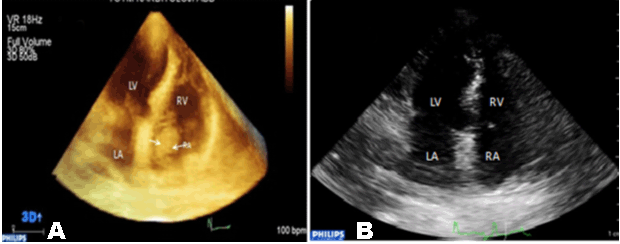

A 53-year-old female patient was admitted to our center because of dyspnea and chest pain. She had a previous history of diabetes mellitus (DM) and had orthotopic liver transplantation (OLT) six months back because of hepatitis B virus (HBV) infection. She presented with a three-week history of chest pain and progressive shortness of breath. Cardiac auscultation was unremarkable, body temperature was 37°C, blood pressure was 130/85 mmHg, heart rate was 85 beats per minute. Respiratory examination and electrocardiogram were normal. Laboratory tests pro-NT brain natriuretic peptide and D-dimer were normal. Lung scan excluded pulmonary embolism. The chest X-ray and computed tomography (CT) scan were normal. CT scan showed a 3.5x1.5x2.5 cm mass in the right atrium near IVC orifice. There was no evidence of deep vein thrombosis on duplex scanning and V/Q scan was negative. Echocardiography showed that the mobile right atrial mass was highly suspicious of a thrombus traversing the right atrial cavity during the cardiac cycle. It was accompanied with free-floating parts of the thrombi. It vertically stretched in the RA and during diastole touched the tricuspid valve (Figures 1A, B). 3DTTE was performed to further confirm the nature of mass. It showed a highly mobile homogenous thrombus, irregular in contour, measuring 3.9×1.8 cm, which originated from IVC and protruding into the RA cavity (Figure 2A). Patient was started on low molecular weight heparin and warfarin. Warfarin dose was adjusted to INR ratio 2–3. The patient had an uneventful hospital course and after one weeks, follow-up the thrombus began to shrink. After three weeks, echocardiography confirmed no evidence of residual thrombus (Figure 2B).

Figure 1: A mass in the right atrium, A) Apical 4-chamber view by TTE, arrow showing stalk of thrombus derived from interior, B) Parasternal short axis view by TTE, thin arrow shows interior vena cava and thick arrow shows stalk of thrombus.